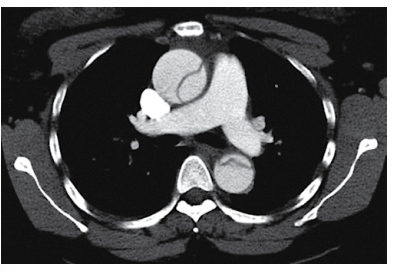

Homem de 49 anos é atendido no pronto-socorro com o relato de dor súbita e intensa no tórax anterior há cerca de 1 hora. O histórico é notável para tabagismo e hipertensão arterial, em uso de enalapril e clortalidona. Nega uso de drogas ou álcool. Ao exame físico: ele encontra-se pálido, sudorético, ansioso, agitado, referindo dor intensa no tórax anterior e posterior; pressão arterial: 194 x 115 mmHg; pulso: 1155 bpm; oximetria de pulso: normal. Glicemia capilar: 125 mg/dL. ECG sem indícios de isquemia. Analgesia intravenosa é prescrita e a angiotomografia de tórax realizada é mostrada a seguir.

Admitindo-se que não há contraindicações, nesse momento, o tratamento parenteral inicial é com